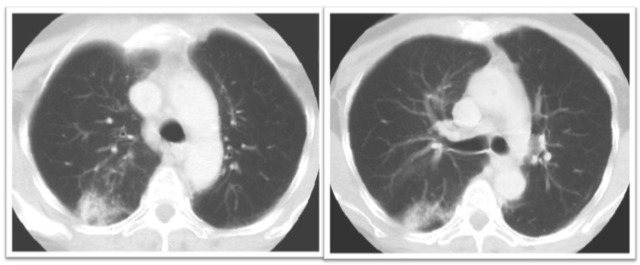

放射性肺炎早中晚期 CT 表现

图 1 右侧乳癌术后放疗 RP:早期表现为照射野内散在的小片状磨玻璃样影、密度淡薄、边缘模糊。

图 2 中期表现为不按肺叶、肺段分布的肺实变,其内可见有支气管充气征,肺泡囊、小叶间隔增厚,部分边缘整齐、部分边缘呈星状,可超出放疗照射野。